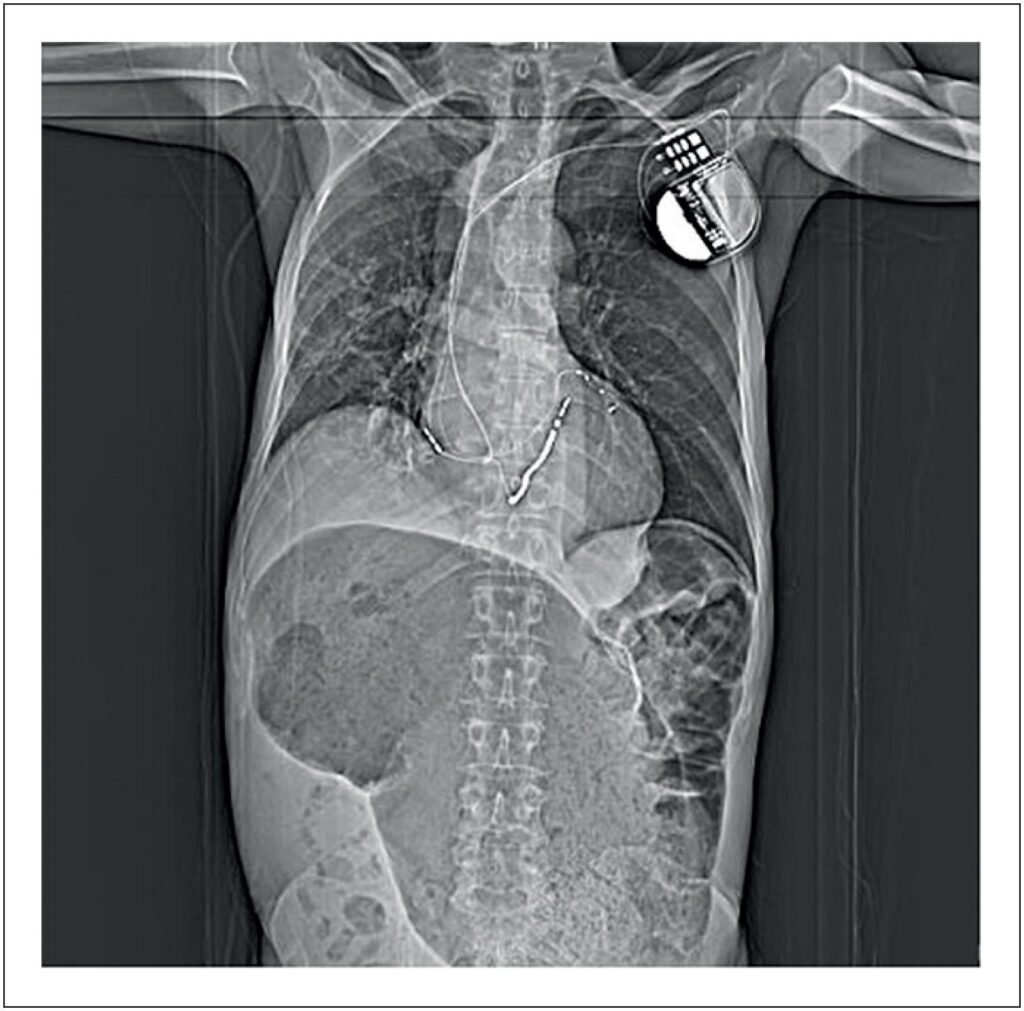

This case concerns a 62-year-old man diagnosed with chagasic cardiomyopathy, presenting with a dilated and arrhythmogenic form, showing significant ventricular dysfunction, and currently undergoing cardiac resynchronization therapy with a previously implanted implantable cardioverter defibrillator. In the outpatient setting prior to admission, the patient’s medical records indicate recurrent ventricular arrhythmias and multiple appropriate shocks from the device over recent years.

Upon admission to the emergency department, the patient complained of severe asthenia, abdominal pain, postprandial vomiting, and choking persisting for a week. His current medication regimen included losartan 100 mg/day, carvedilol 50 mg/day, spironolactone 25 mg/day, empagliflozin 25 mg/day, furosemide 80 mg/day, acetylsalicylic acid 100 mg/day, and atorvastatin 40 mg/day. During the physical examination upon admission, a significant drop in general condition, cachexia, blood pressure of 84×57 mmHg, and heart rate of 93 bpm were observed. In addition to hypotension, cold extremities and prolonged capillary refill time were noted. There were no peripheral edema, jugular distension or pulmonary congestion. In addition, there was significant abdominal distension and pain on palpation. Based on the patient’s clinical history and physical examination findings, a diagnosis of acute obstructive abdomen and decompensated heart failure (HF) with an L-profile was determined.